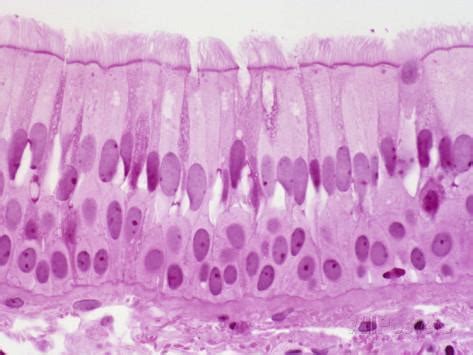

Pseudostratified Ciliated Columnar / / The cells that comprise the epithelial membranes are variously shaped and are named accordingly.. Includes secretory, nonciliated cells (with basal nuclei). Its function is to protect these trachea composes of pseudostratified columnar, ciliated epithelium, goblet cells. Pseudostratified ciliated columnar epithelium consists of a single layer of cells. A pseudostratified columnar epithelium is a tissue formed by a single layer of cells that give the appearance of being made from multiple layers, especially when seen in cross section. Find out information about pseudostratified ciliated columnar epithelium.

Epithelial tissue lines the inner and outer surfaces of organs in the body and function in processes of secretion, absorption. A type of epithelium in which all cells reach to the basement membrane but some extend toward the surface only part way. The pseudostratified columnar epithelium is found in different parts of the body and each specific location serves different functions. The cells that comprise the epithelial membranes are variously shaped and are named accordingly. Ciliated pseudostratified columnar epithelia is found lining the trachea and upper respiratory tract.

Ciliated pseudostratified columnar epithelia is the type of respiratory epithelium found in the linings of the trachea as well as the upper respiratory tract. Pseudostratified ciliated columnar epithelium consists of a single layer of cells. Epithelial tissue lines the inner and outer surfaces of organs in the body and function in processes of secretion, absorption. Learn about pseudostratified ciliated columnar epithelium with free interactive flashcards. Pseudostratified ciliated epithelium lines the nasal cavities, trachea, and bronchi. Posteriorly, the epithelium is a pseudostratified ciliated columnar epithelium that covers the respiratory regions (formed by the maxilloturbinates).45,107,110 the superior turbinate. As it rarely occurs as squamous or cuboidal epithelia. Cliffsnotes states that the pseudostratified characterization comes from the fact that ciliated columnar epithelium cells appear to have multiple layers when there is actually just one cell.

This gives the appearance of multiple layers. Epithelial tissue lines the inner and outer surfaces of organs in the body and function in processes of secretion, absorption. 200 to 300 cilia per cell; Lines the nasal cavities, trachea, and bronchi by secreting mucus by goblet cells and move mucus with cilia. + pseudostratified columnar epithelial tissue. Histology of trachea histology slide of trachea histological slide of trachea. Pseudostratified ciliated columnar epithelium video. A pseudostratified epithelium is a type of epithelium that, though comprising only a single layer of cells, has its cell nuclei positioned in a manner suggestive of stratified epithelia. The cells that comprise the epithelial membranes are variously shaped and are named accordingly. The respiratory airways are lined by a pseudostratified columnar epithelium with a variety of distinct cell types including. As it rarely occurs as squamous or cuboidal epithelia. Crogvpseudostratified columnar tumor cells present. Ciliated pseudostratified columnar epithelia is the type of respiratory epithelium found in the linings of the trachea as well as the upper respiratory tract.

Unlike simple columnar epithelium, the nuclei are arranged at different levels within the cells. Pseudostratified ciliated epithelium lines the nasal cavities, trachea, and bronchi. Histology of trachea histology slide of trachea histological slide of trachea. Pseudostratified ciliated columnar epithelium cells function as a protective layer in the respiratory system of humans. Note the ciliated, pseudostratified columnar epithelium lining the tracheal lumen.

Includes secretory, nonciliated cells (with basal nuclei). Pseudostratified ciliated columnar epithelium video. Note the ciliated, pseudostratified columnar epithelium lining the tracheal lumen. This gives the appearance of multiple layers. Lines the nasal cavities, trachea, and bronchi by secreting mucus by goblet cells and move mucus with cilia. Learn about pseudostratified ciliated columnar epithelium with free interactive flashcards. Pseudostratified ciliated columnar epithelial cell. Epithelial tissue lines the inner and outer surfaces of organs in the body and function in processes of secretion, absorption. Unlike simple columnar epithelium, the nuclei are arranged at different levels within the cells. Histology of trachea histology slide of trachea histological slide of trachea. Trachea histology slide) click to enlarge. Cliffsnotes states that the pseudostratified characterization comes from the fact that ciliated columnar epithelium cells appear to have multiple layers when there is actually just one cell. As it rarely occurs as squamous or cuboidal epithelia.

The pseudostratified columnar epithelium is found in different parts of the body and each specific location serves different functions. The trachea is lined with ciliated pseudostratified columnar epithelium. In some columnar epithelia, the cells become so crowded that some of the nuclei become displaced and several rows of nuclei appear in sections of the cell sheet. Pseudostratified ciliated epithelium lines the nasal cavities, trachea, and bronchi. A pseudostratified columnar epithelium is a tissue formed by a single layer of cells that give the appearance of being made from multiple layers, especially when seen in cross section.

The respiratory airways are lined by a pseudostratified columnar epithelium with a variety of distinct cell types including. Pseudostratified ciliated epithelium lines the nasal cavities, trachea, and bronchi. Includes secretory, nonciliated cells (with basal nuclei). The trachea is lined with ciliated pseudostratified columnar epithelium. Ciliated pseudostratified columnar epithelia is the type of respiratory epithelium found in the linings of the trachea as well as the upper respiratory tract. The pseudostratified columnar epithelium is found in different parts of the body and each specific location serves different functions. This gives the appearance of multiple layers. Pseudostratified ciliated columnar epithelial cell.

Pseudostratified ciliated columnar epithelium consists of a single layer of cells. A pseudostratified columnar epithelium is a tissue formed by a single layer of cells that give the appearance of being made from multiple layers, especially when seen in cross section. Pseudostratified columnar epithelia are found forming the straight, tubular. A pseudostratified epithelium is a type of epithelium that, though comprising only a single layer of cells, has its cell nuclei positioned in a manner suggestive of stratified epithelia. Ciliated pseudostratified columnar epithelia is the type of respiratory epithelium found in the linings of the trachea as well as the upper respiratory tract. Histology of trachea histology slide of trachea histological slide of trachea. A type of epithelium in which all cells reach to the basement membrane but some extend toward the surface only part way. As it rarely occurs as squamous or cuboidal epithelia. The cells that comprise the epithelial membranes are variously shaped and are named accordingly. The trachea is lined with ciliated pseudostratified columnar epithelium. Ciliated pseudostratified columnar epithelia is the type of respiratory epithelium found in the linings of the trachea as well as the upper respiratory tract. It is said to be pseudostratified (pseudo = false) because its structure creates a visual illusion of being multilayered. Pseudostratified ciliated columnar epithelium cells function as a protective layer in the respiratory system of humans.

+ pseudostratified columnar epithelial tissue pse. It is said to be pseudostratified (pseudo = false) because its structure creates a visual illusion of being multilayered.